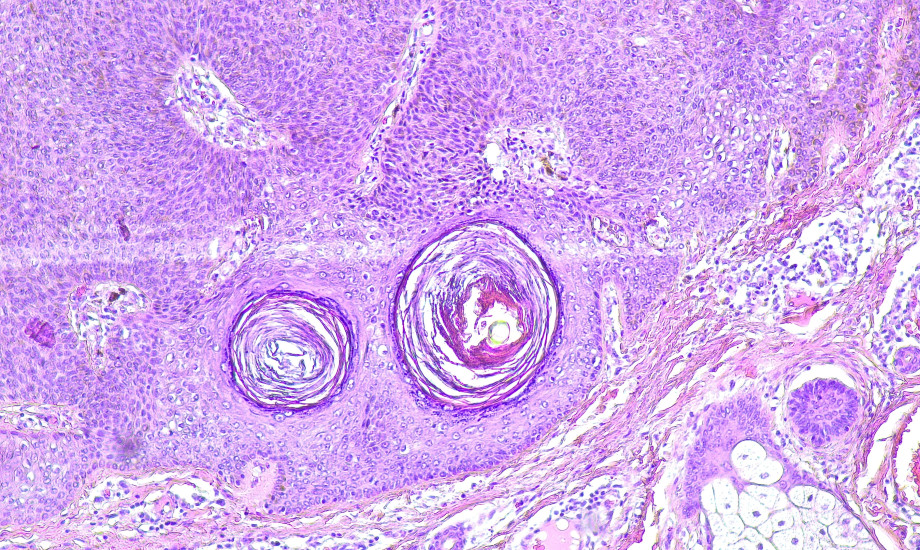

Eine Patientin entwickelt während ihrer Schwangerschaften eine sehr große, auffällige Läsion, die den gesamten Mamillen-Areolen-Komplex einnimmt und den Verdacht auf eine maligne Erkrankung weckt. Nach histologischer Aufarbeitung kann jedoch Entwarnung gegeben werden.